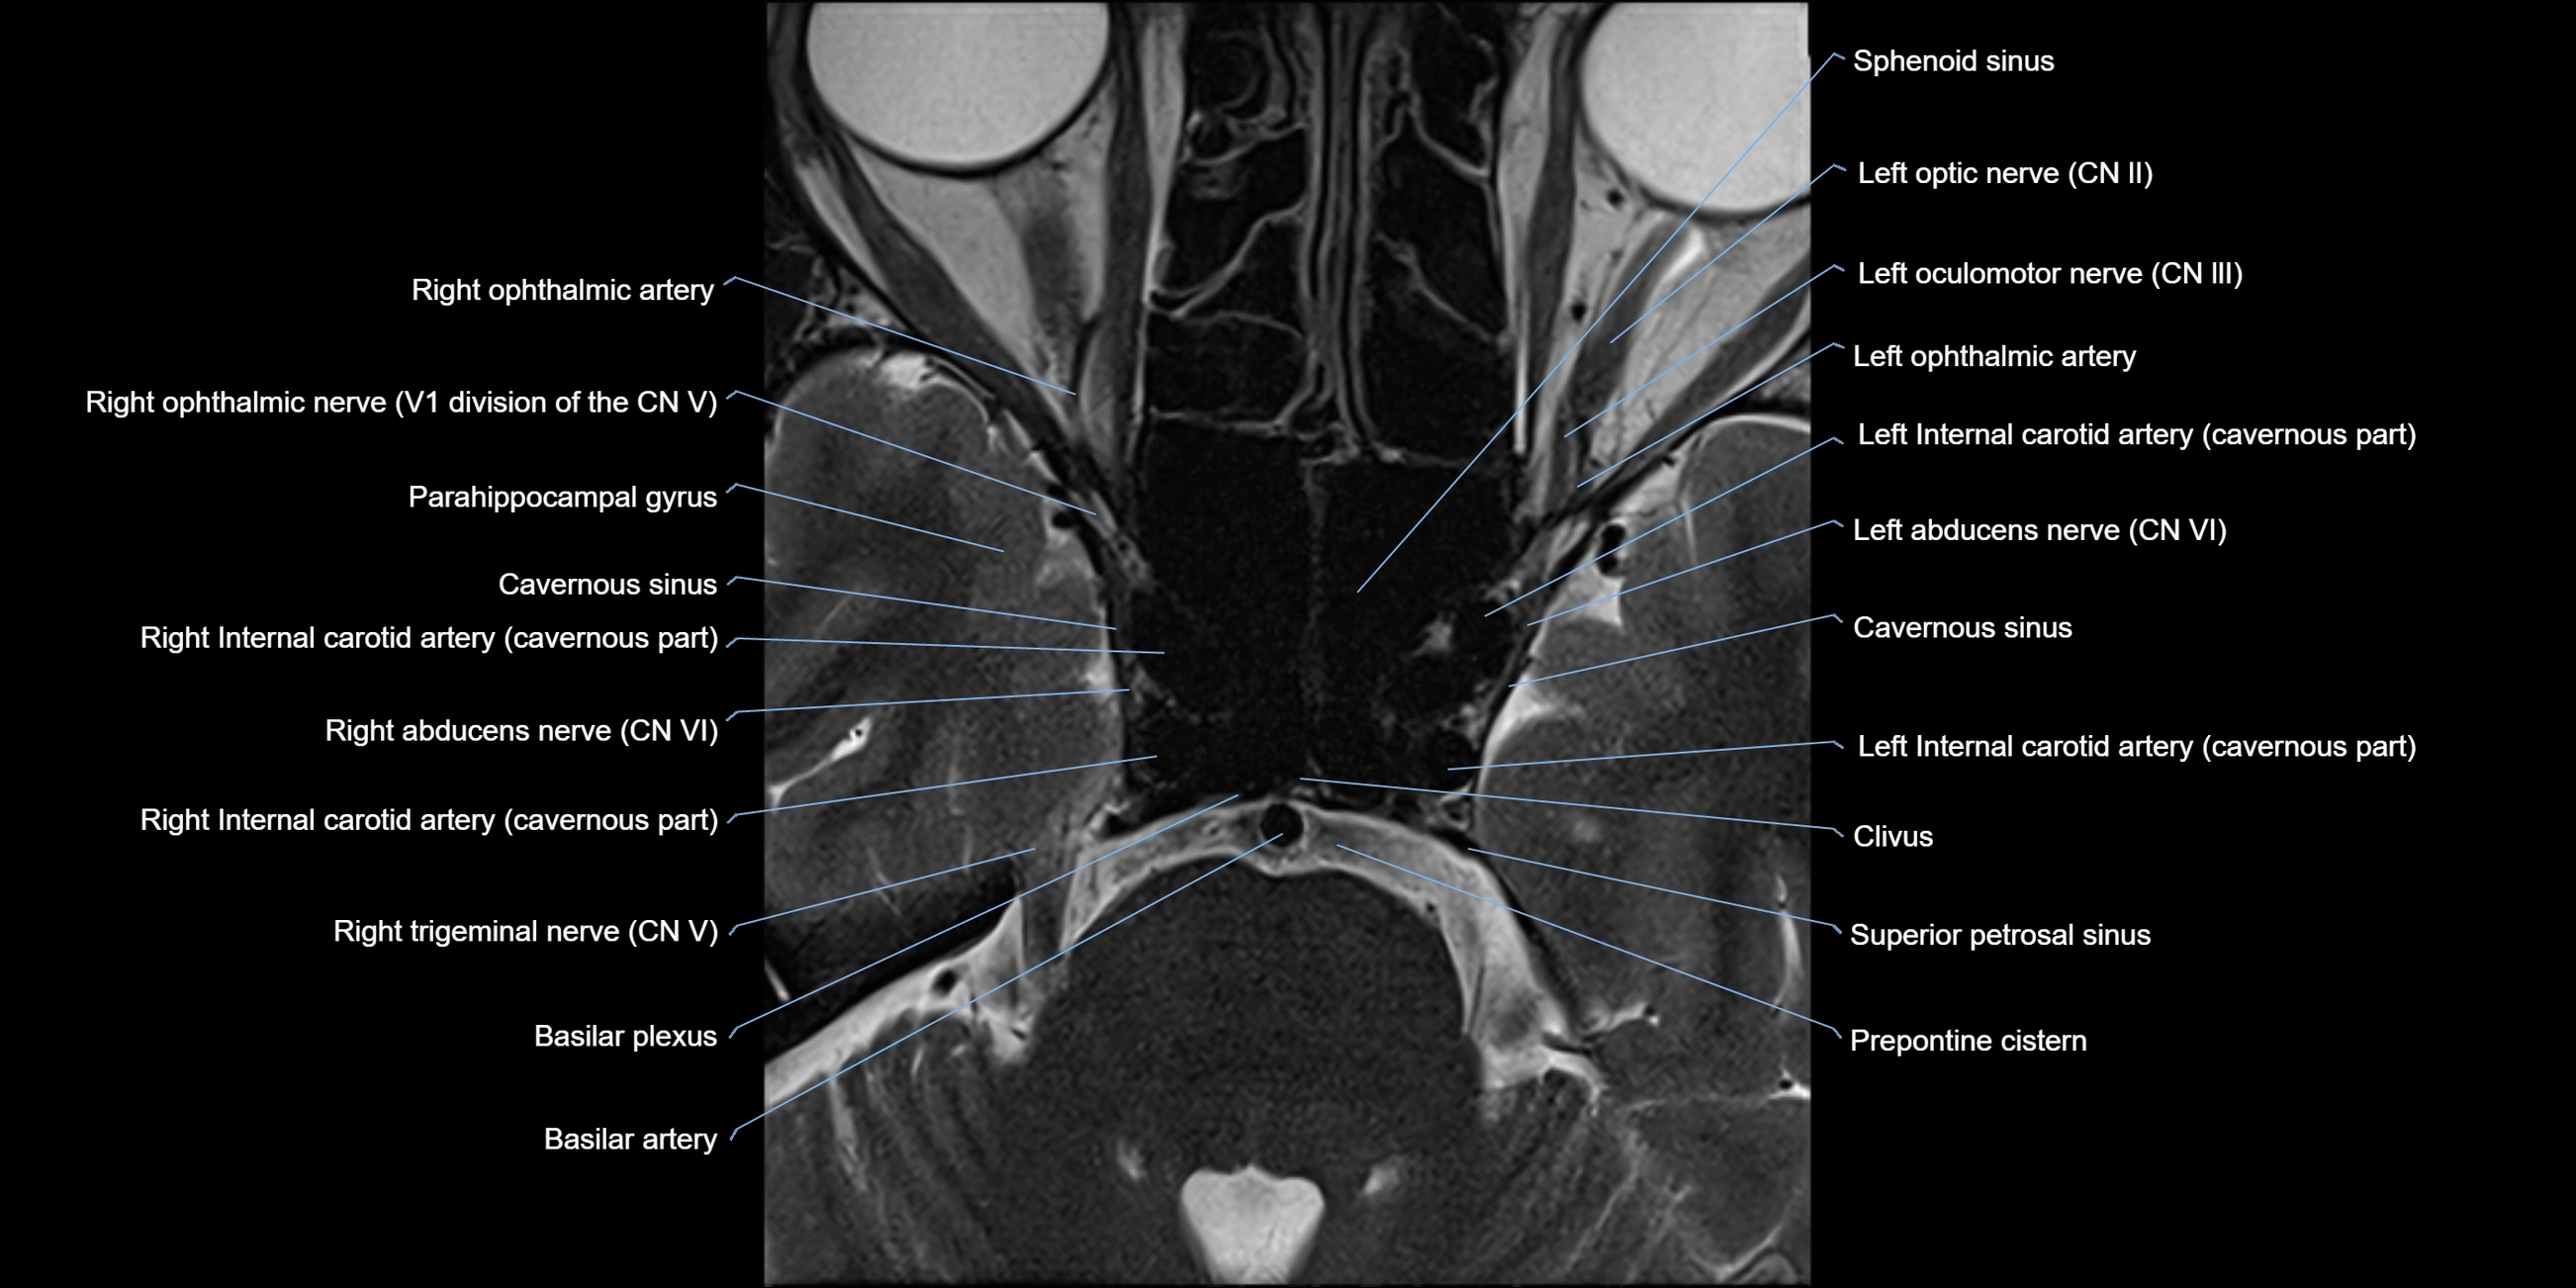

MRI Appearance

The abducens nerve is a small, thin, linear structure

Best visualized on high-resolution T2-weighted 3D MRI sequences (e.g., FIESTA or CISS)

Seen as a hypointense (dark) line running from the brainstem at the pontomedullary junction, traversing the prepontine cistern, and entering Dorello’s canal under the petrosphenoidal ligament, then into the cavernous sinus, and finally the orbit

May be challenging to visualize in standard MRI due to its small size

Pathology may be inferred by absence, displacement, or enhancement of the nerve

MRI images